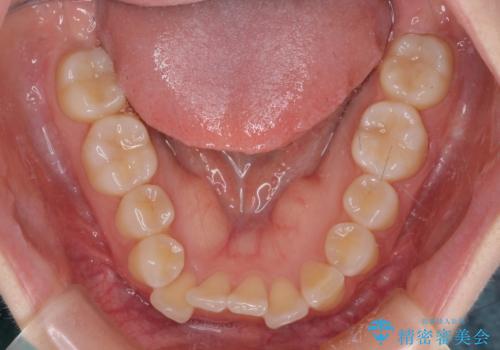

- 上下前歯のデコボコを気にして来院された患者様です。

ワイヤー矯正でもインビザライン矯正でも対応可能でしたが、インビザラインでの自己管理の煩わしさを避けるため、ワイヤー装置にて矯正治療を行うこととしました。

患者様も驚く、僅か10か月での治療終了となりました。

下顎前歯が1歯欠損しているため、上下正中は合わず、左右奥歯の咬み合わせは理想的とはならない仕上がりとなります。